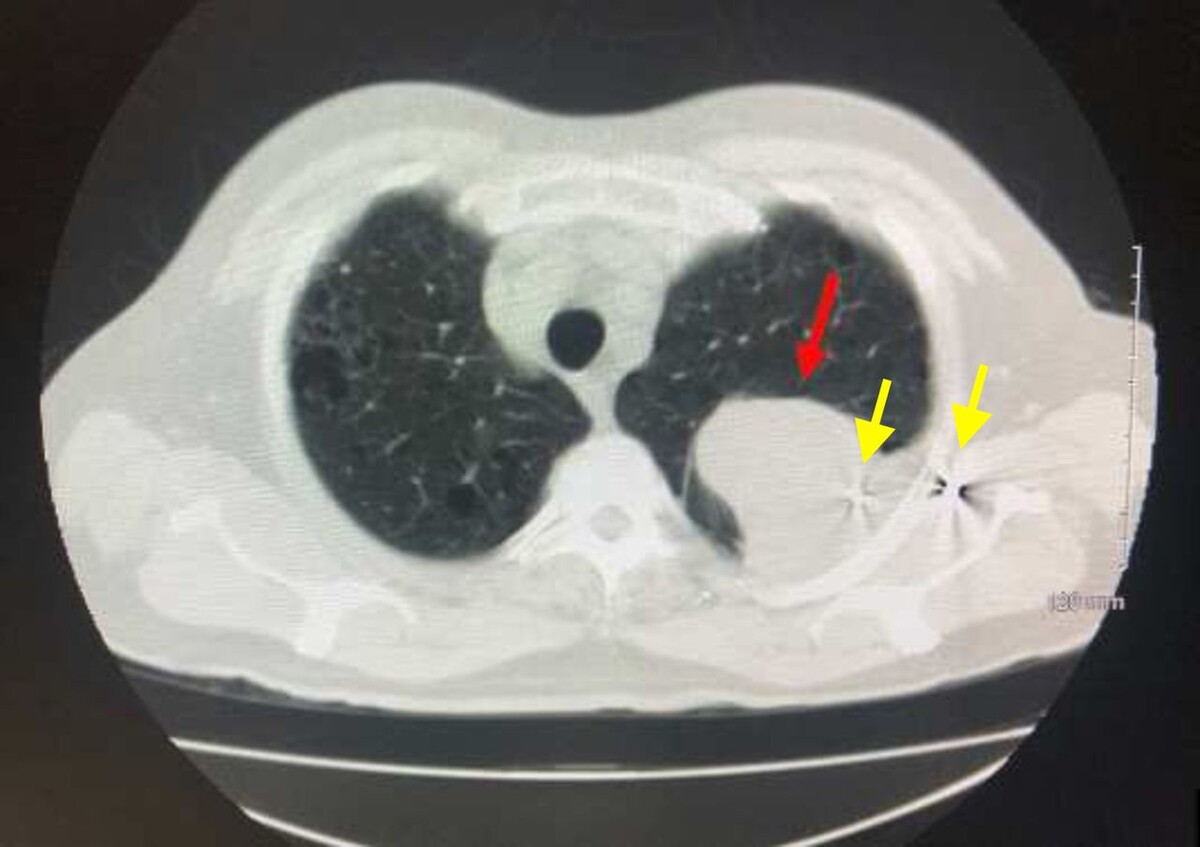

При дополнительном обследовании в его левом легком было обнаружено образование размером 7,6 × 7,5 сантиметра и баллистические осколки в этом образовании, левой подмышечной впадине и заднем средостении, которые сохранились у него после огнестрельного ранения, полученного 45 лет назад. В анамнезе у пациента не числилось онкологических заболеваний, однако он страдал гипотиреозом и дислипидемией. Также мужчина сообщил, что он употреблял табак в течение 37,5 года, но бросил курить три десятилетия назад.

Позитронно-эмиссионная томография выявила изолированное образование в левой верхней доле легкого с локальным поражением грудной стенки без признаков метастазирования. Биопсия легкого подтвердила диагноз мелкоклеточного рака легкого. Врачи удалили пораженную долю легкого вместе с регионарными лимфоузлами.